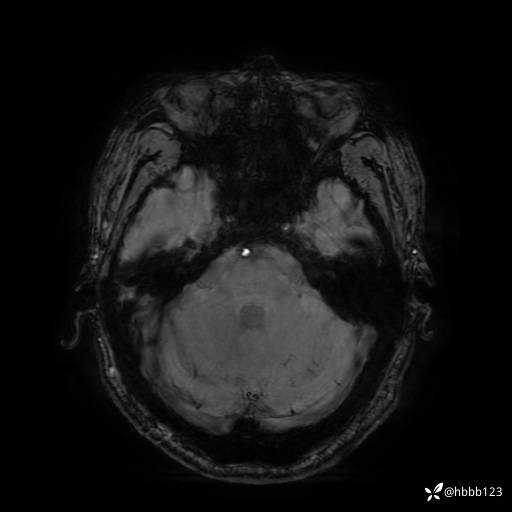

SWAN: